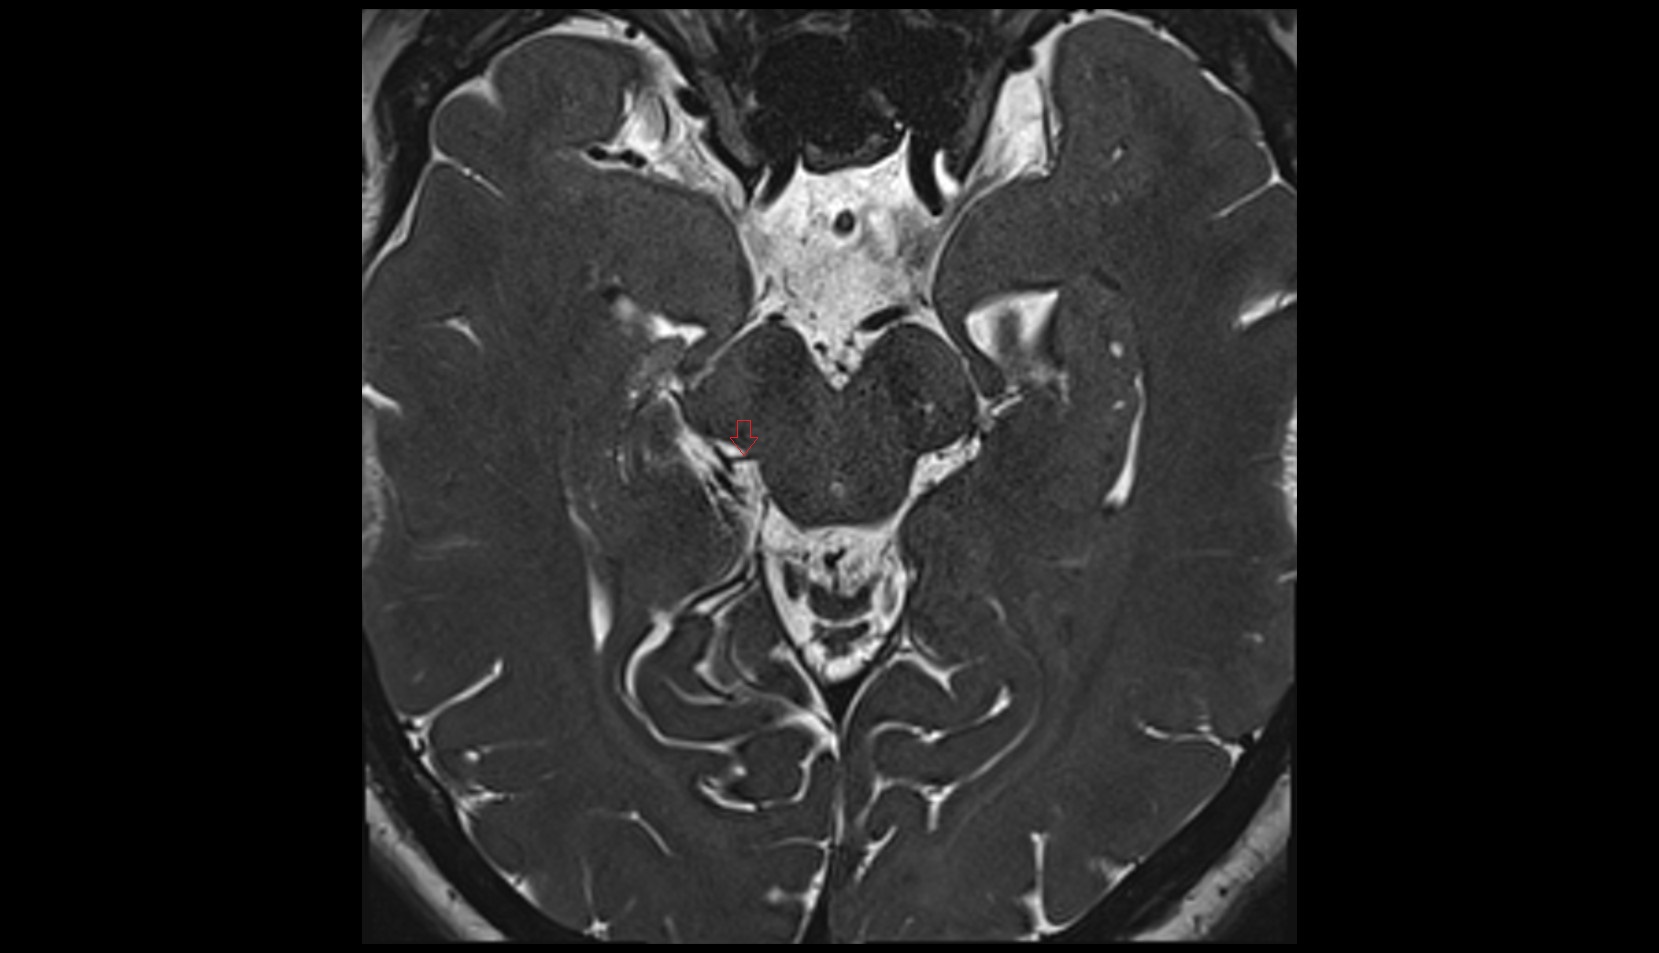

- Cerebellum

- Tonsil of cerebellum

- Posterior cerebellomedullary cistern (cisterna magna)

- Cisterna magna